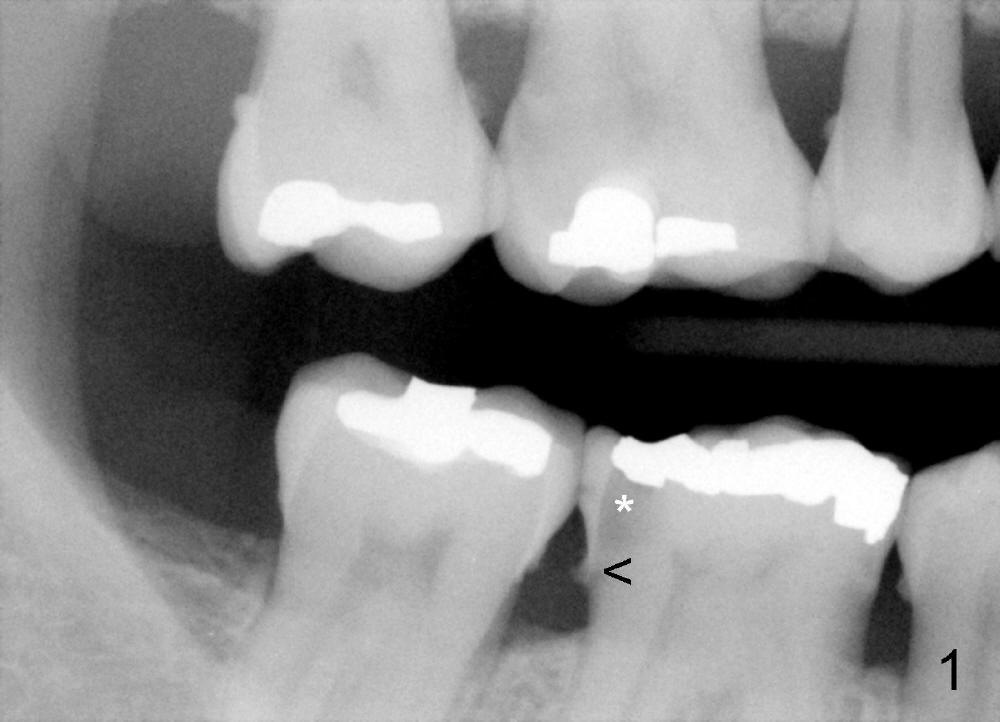

Dowman太太来自德国,收入不好,抽烟,不用牙线,结石多(图一箭头),右下第一磨牙远中龋齿(*)。她深洗还积极(图二已经没有明显结石),处理龋齿拖拖拉拉,九个月后,去龋时穿髓,暂封(图二*),她的后牙牙根特长,说明什么?下面回答。不得不做根管治疗(图三),图四是根管治疗后一年半拍摄,虽然根尖有阴影(箭头),但是病人没有任何症状。又过两年多病人主诉右下不适,根尖片显示根分叉阴影特大(图五*),近中根近中也有阴影(箭头),这时结石又出现。口内检查太容易了:右下第一磨牙颊侧有瘘道(图六双箭头),颊侧根分叉上皮附着失去(图六单箭头,也就是牙周袋深,探测出血),而舌侧根分叉牙周袋正常。总之,近中根有隐裂,接近颊侧,而远中根好像不容易出事,因为它比近中根粗。当我们为她牙齿惋惜时,老外比较爽快,说“It is not your fault. I love eating nuts. I grind my teeth at night. My night guard is too old to wear”。这段话可能说明为什么她后牙牙根长。